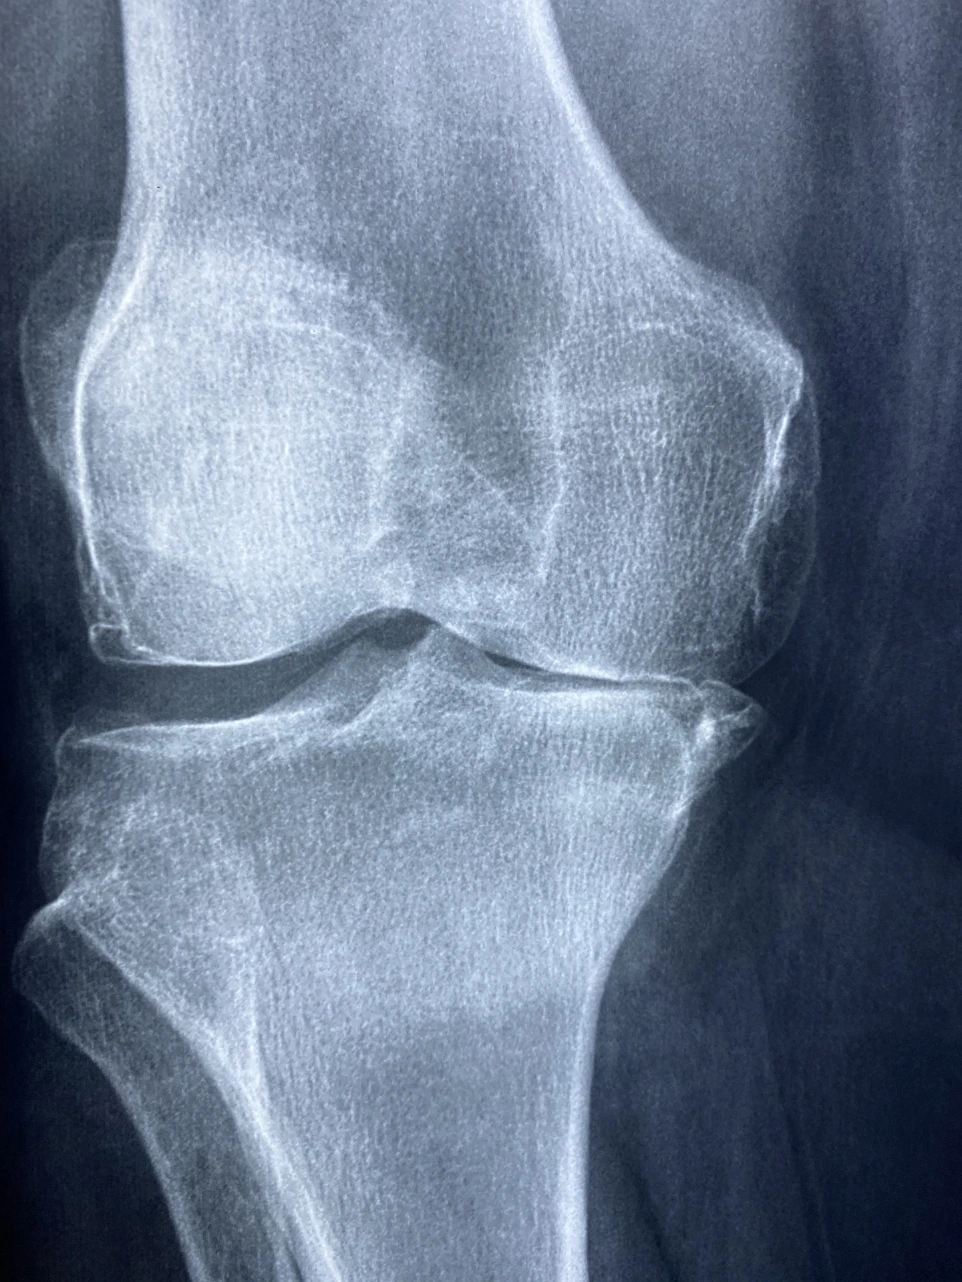

Trong cơ xương khớp, y học tái tạo thường được nghiên cứu để hỗ trợ các tình trạng như:

• thoái hóa khớp gối, khớp háng

• tổn thương sụn khớp

• thoái hóa khớp giai đoạn sớm – trung bình

• bệnh nhân thoái hóa khớp mức độ vừa

• chưa cần thay khớp ngay